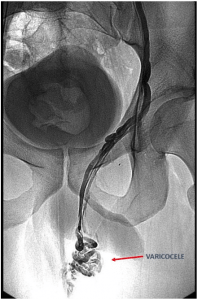

Varicocele